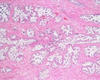

3

Q

A

Liver